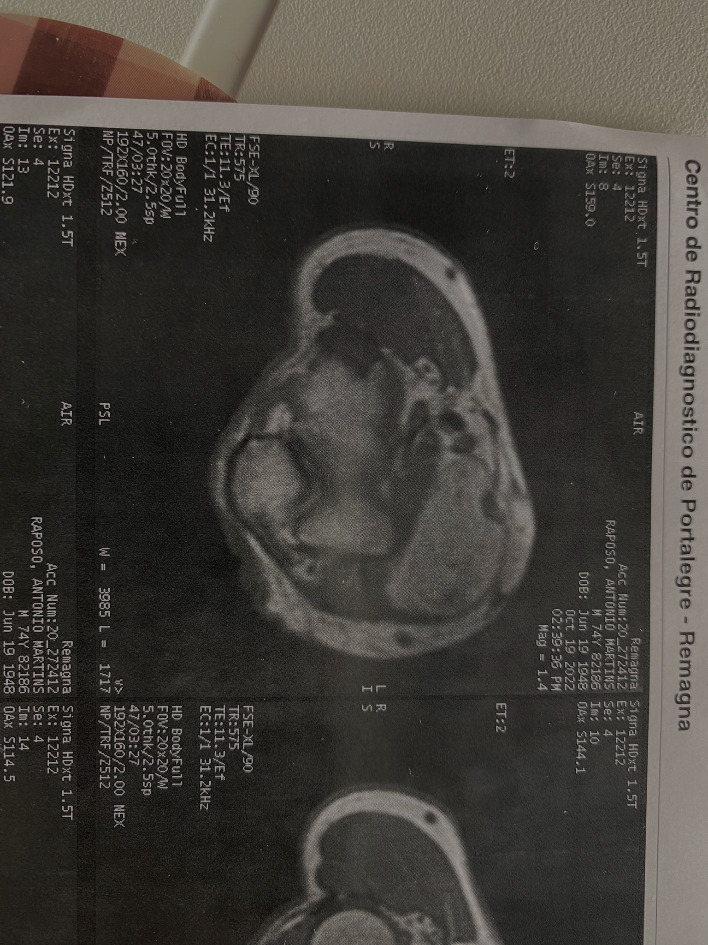

In June of 2022, the patient returned, maintaining hand paresthesia but with bigger lack of grip strength, impacting more severely his daily activities. Clinically, a bigger nodule was palpated in the proximal volar right forearm. A magnetic resonance imaging (MRI) study was performed (figure 3) and described the lesion as a large ovoid formation with increased signal in T1 and T2 with vanishing signal in the fat suppression sequences. The lesion dimensions were 19x6x3.5 centimeters, deep and medial to the biceps bracchi tendon, causing proximal anterolateral deviation of the median nerve.